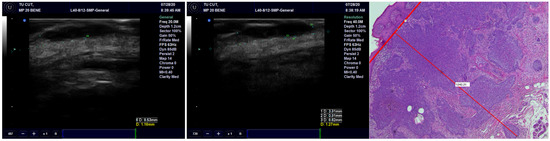

Concerning concordance between the histopathological and echographic measurements of tumor thickness, we found excellent agreement for all transducers, with the best ones being for the preoperative observations and the least favorable ones being the postoperative observations (Figure 3) (Table 2). Within any of the preoperative and postoperative observations, the 40 MHz transducer fared the best, followed by the 20 MHz transducer and finally by the 13 MHz transducer.

Figure 3.

The thickness of the tumor, measured on US with 20 MHz and 40 MHz transducers, compared with the pathological image of the tumor showing very high occurrence of US.

We found a very high correlation between the ultrasound measurement of the surgical margins and pathological reports, with the best result being achieved with the 13 MHz transducer, followed by the 20 MHz and 40 MHz transducers (Figure 8) (Table 5).

Figure 8.

Surgical margins measurement by US and histopathology.